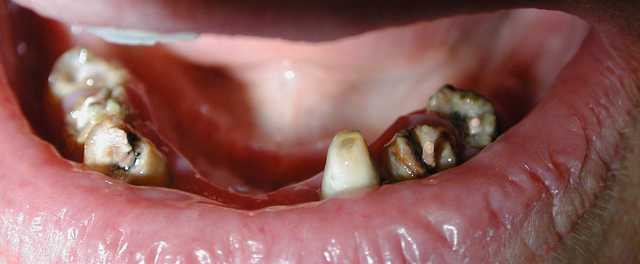

Voila un cas vite fait par un rentable: ramolli en 5 ans

Tu penses qu'on peut le rattraper en faisant inlay-core + bridge ?

Tu penses que j'ai perdu mon temps pour justifier des séances ?